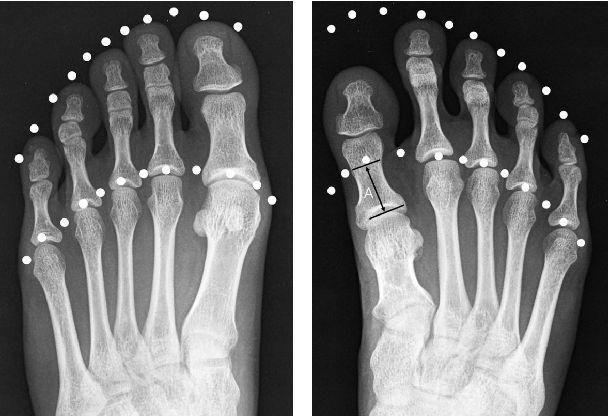

先天性第四跖骨短小症

先天性第四跖骨短小症,先天性高肩胛骨症图片

脚趾短小怎么办?

一次性手术治疗先天性跖骨短小症